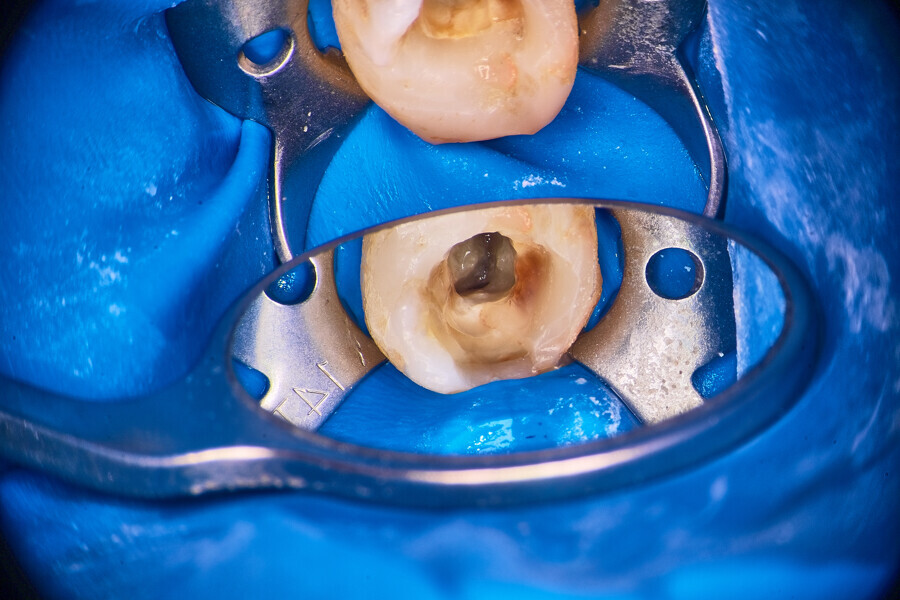

Under local anaesthesia, a dental dam was placed, and the field was sealed with liquid dental dam (RUBBER-DAM liquid, CERKAMED; Fig. 2). The temporary restoration was removed. The pulp chamber was irrigated with distilled water and sodium hypochlorite 5,25% activated with ultrasonic tips (Fig. 3). The first mesiobuccal (MB1), DB and palatal (P) canals were patent, so I was able to establish the working length with the C-PILOT file (VDW) and an apex locator (E-PEX, Eighteeth). The canals were shaped up to approximately two-thirds of the working length with the 25/0.07 Perfect Shape reciprocating file (Shenzhen Perfect Medical Instruments). The dentine above the orifice of the MB2 canal was removed using a diamond-coated ultrasonic tip (ED3D, Woodpecker), revealing an isthmus located between the MB1 and MB2 canals. Preparation of the orifice of the MB2 canal was possible only in the coronal third with a hand file (Fig. 4). The isthmus between both canals was removed for an additional 2 mm in depth also with the diamond-coated tips (Fig. 5).

Fig. 2

Fig. 3

Fig. 4

Fig. 5